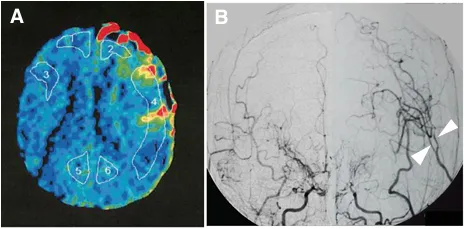

术前血管造影(双侧颈总动脉正位图)显示双侧颈内动脉末端有“烟雾血管狭窄征象”,双侧大脑中动脉(MCA)狭窄(左)。术前Xe-CT显示双侧MCA区域脑血流减少(右)

小玉的手术成功了,术后影像显示,左MCA区域的高血流灌注现象(图A),但未发生额外的缺血性和出血性并发症(图B,C)。无任何新发缺血或出血病灶。

术后,小玉的恢复令人欣慰。她的神经功能显着改善,MRS评分从术前的4分(重度残疾)恢复到2分(轻度残疾),重新获得了独立生活的能力。

术后20天血管造影显示,桥血管通畅,血流通畅;23天后的MR复查确认,未出现新的脑梗死或出血灶。